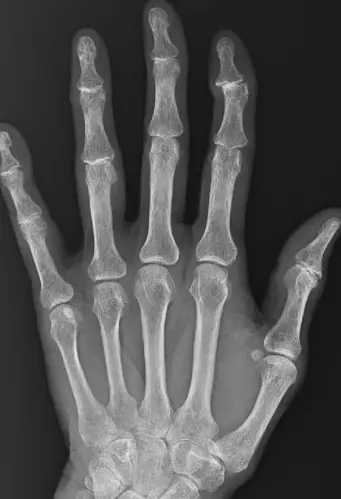

正常な母指CM関節。

母指CM関節がずれている。

『母指CM関節症』が進んだ状態。ゴツゴツとした見た目に。

正常な第一関節。

人さし指の第一関節にずれが生じることで曲がる。

『へバーデン結節』の炎症が進み、第一関節が曲がったケース。